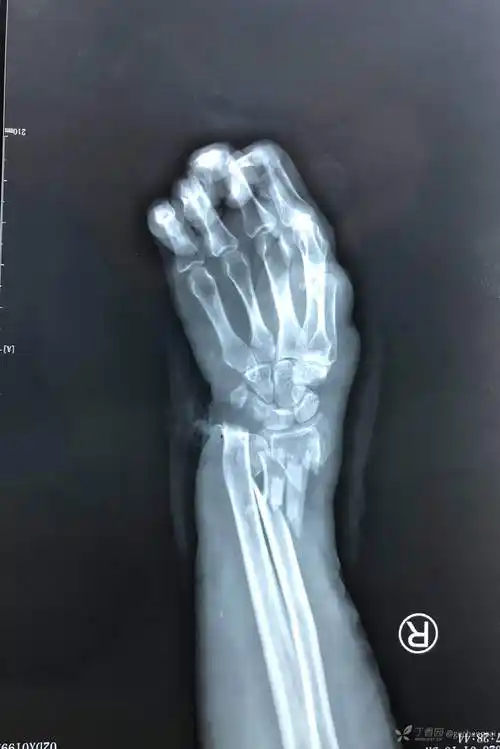

开放性尺桡骨远端粉碎性骨折